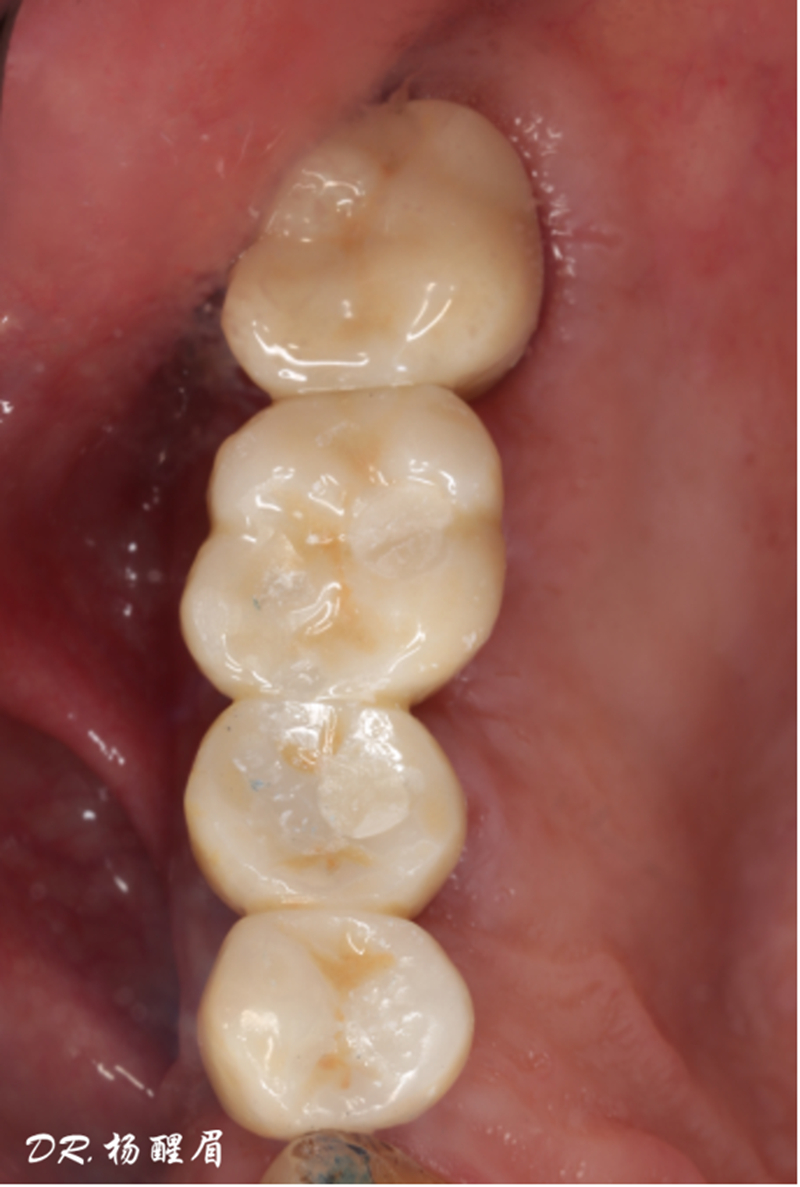

®袖口形態(tài)

®基樁形態(tài)

修復完成